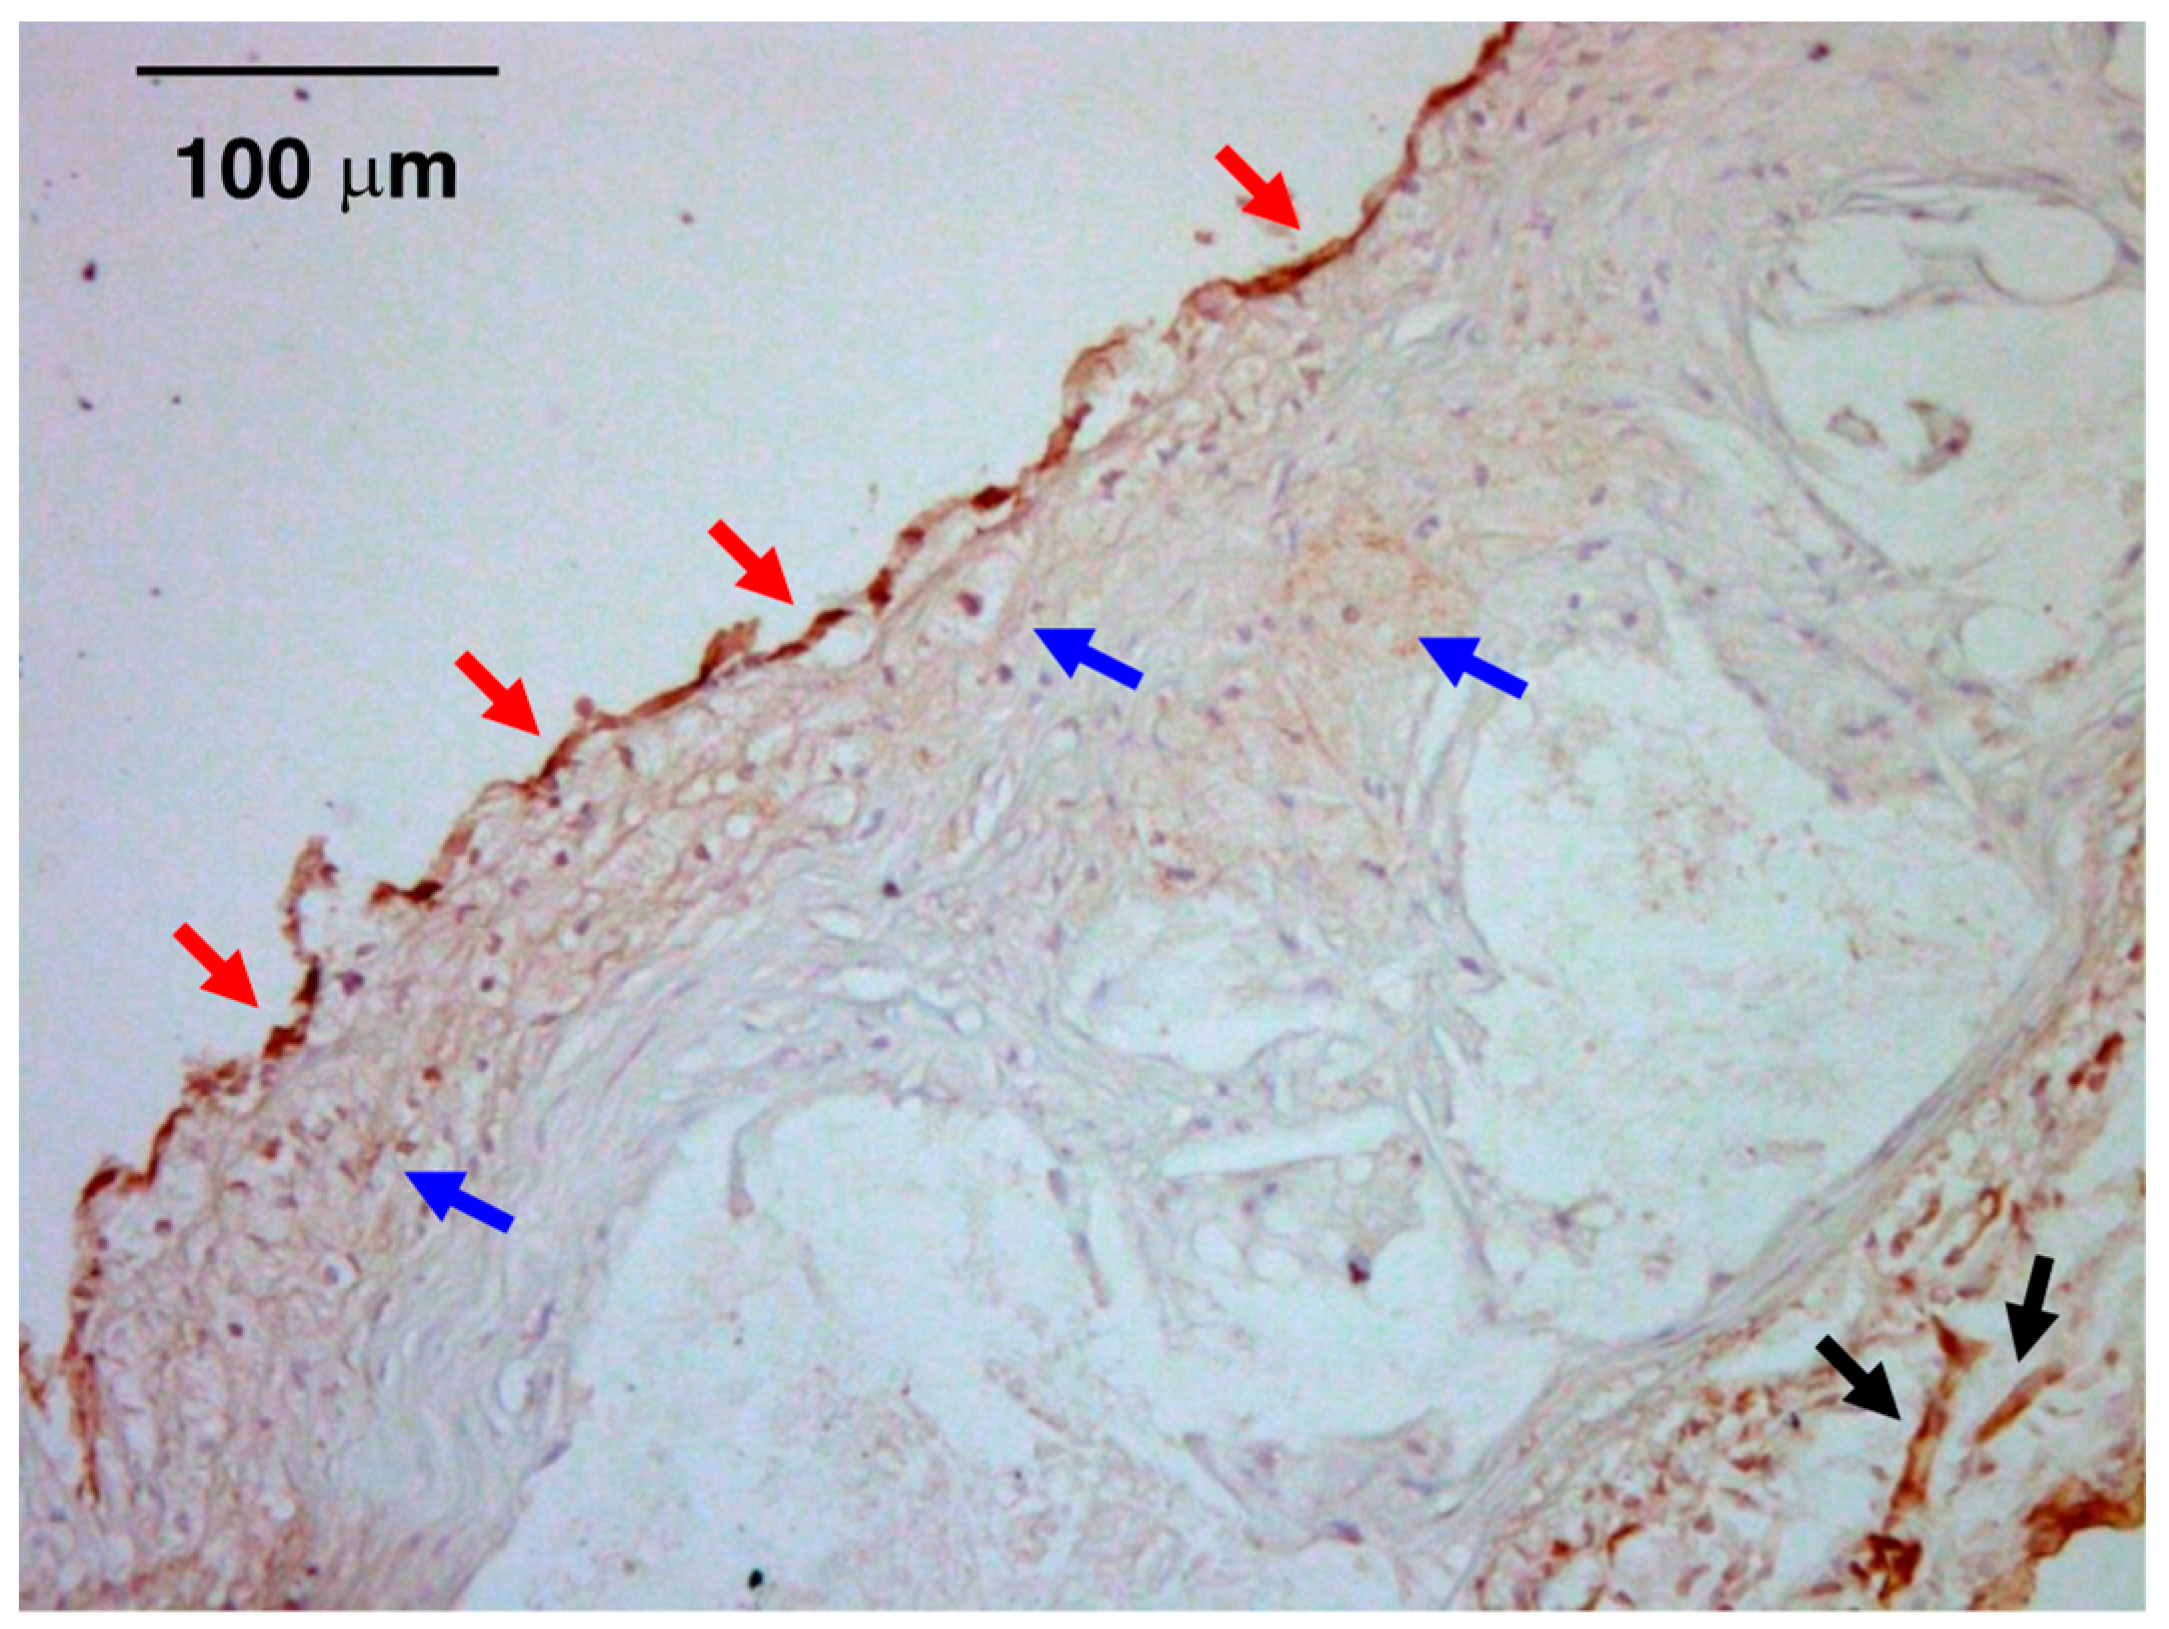

6. Atheroprone Effects of CT-1

- Konii, H.; Sato, K.; Kikuchi, S.; Okiyama, H.; Watanabe, R.; Hasegawa, A.; Yamamoto, K.; Itoh, F.; Hirano, T.; Watanabe, T. Stimulatory effects of cardiotrophin 1 on atherosclerosis. Hypertension 2013, 62, 942–950. [Google Scholar] [CrossRef] [PubMed]